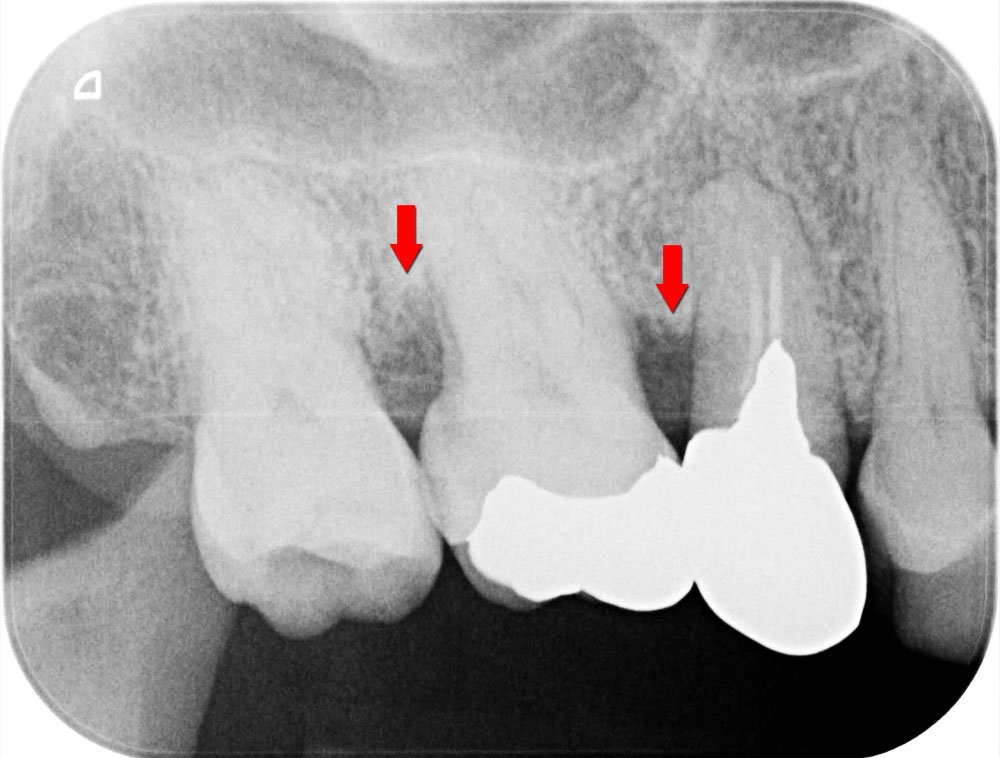

歯周再生治療前

お口全体の徹底した歯石除去をおこないます。その後歯科衛生士による歯ブラシ指導をおこない患者さんのホームケアの質を高めた上で、歯周病の精密検査を行います。基本歯周治療によって歯周病の改善がみられていることを確認のうえ、歯周再生療法に移行します。レントゲン写真の矢印部箇所のように、骨が歯周病により溶けている状態です。